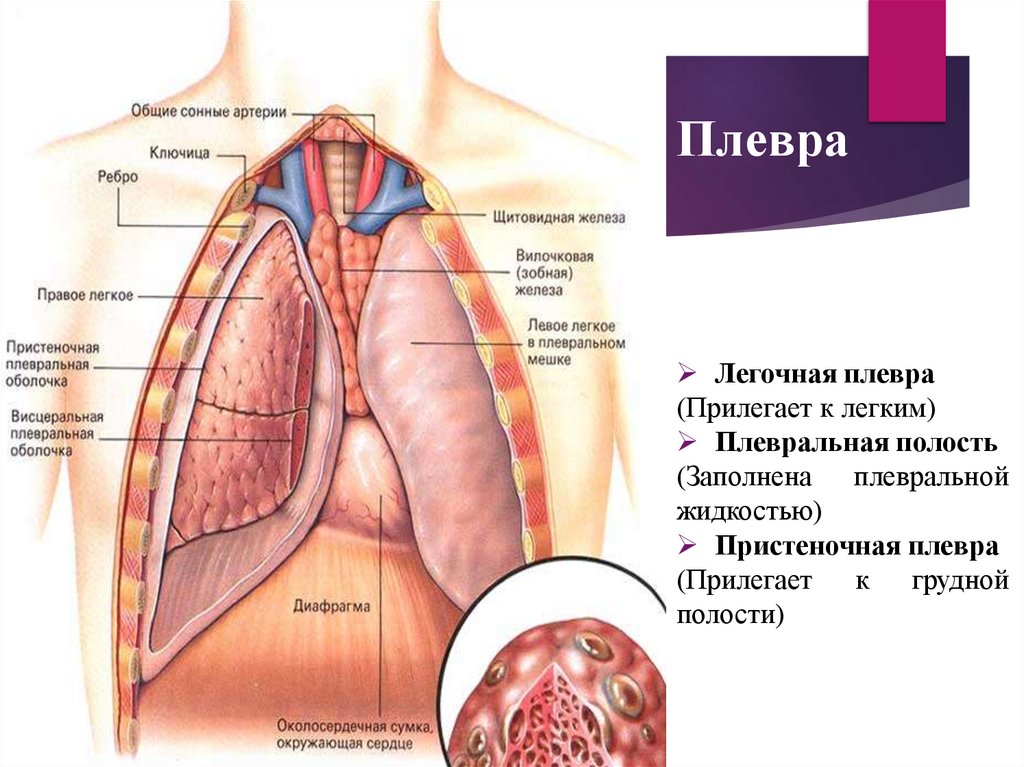

Роль легких в метаболических процессах